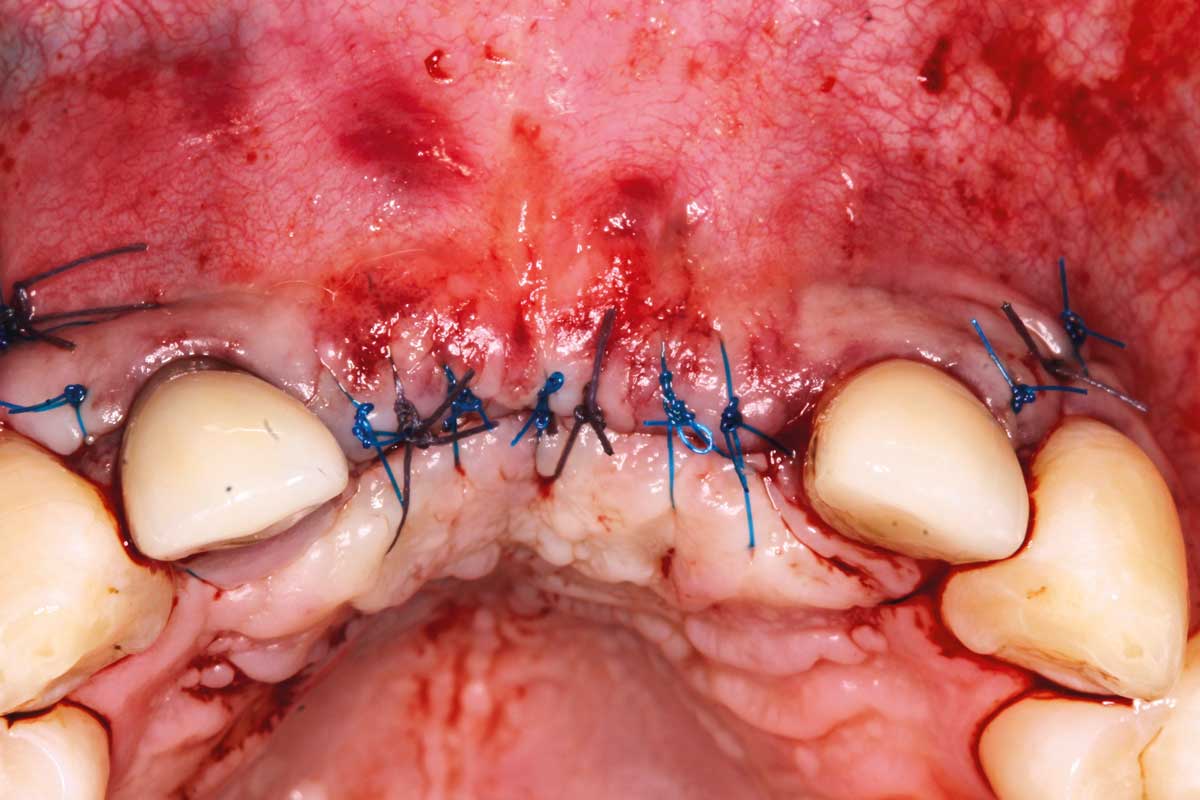

09/26 - Wound closure with 15 sutures

Ridge augmentation in the maxilla with maxgraft® bonebuilder in the aesthetic zone - Dr. M. Kristensen